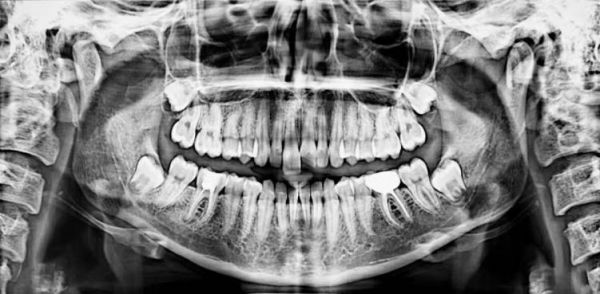

任何成功的手術(shù)都始于精密的術(shù)前規(guī)劃。在種植牙領(lǐng)域,錐形束CT(CBCT)  是實現(xiàn)精準(zhǔn)規(guī)劃不可或缺的基石。它徹底告別了傳統(tǒng)X光片的“平面猜謎”,能夠提供您頜骨的三維立體影像,就好比為醫(yī)生提供了一份您口腔的“透明地圖”或“導(dǎo)航地圖”。通過這份高精度的“地圖”,醫(yī)生可以:

精確評估“地基”條件:能夠精確測量缺牙區(qū)牙槽骨的高度、寬度、密度,就像建筑師勘察土地一樣,判斷“土壤”是否肥沃堅實,是否滿足種植條件,或是否需要先行植骨(“改良土壤”)。

安全規(guī)避“地下管線”:能清晰顯示下牙槽神經(jīng)管、上頜竇底、血管等重要解剖結(jié)構(gòu)的位置。術(shù)前拍攝CBCT,能夠了解口腔神經(jīng)走向、血管分布、上額竇位置、牙槽骨狀況等,是制定安全、精準(zhǔn)手術(shù)方案的基石。這相當(dāng)于在施工前就明確了所有地下管線的分布,從而在植入種植體時能夠精準(zhǔn)避開,極大提升了手術(shù)的安全性,從源頭上避免了盲目操作可能帶來的神經(jīng)損傷、上頜竇穿孔等風(fēng)險。